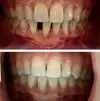

Zirkonyum uygulamalar

Porselen uygulamaları

Laminate veneer